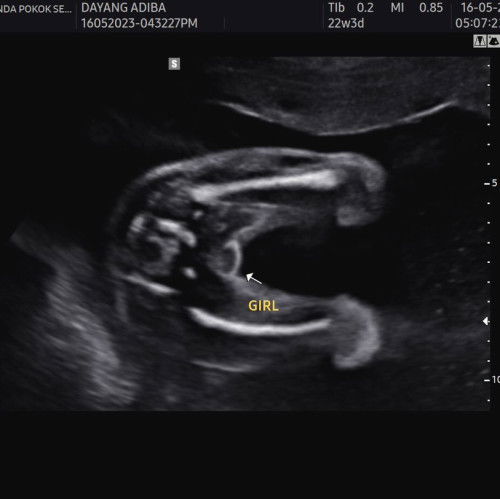

Gender baby

Assalammualaikum. Hi semua. Saya first mum. Lepas 2 kali gugur. Alhamdulillah pregnant kali ke-3 ni dah 6 bulan lebih. Haritu scan baby terus dia kangkang tunjuk gender dia. Doc cakap confirm girl. Betul ka mommy semua ? 🥺. Risau kena scam. Nak pi beli baju baby ni hehe.

kalau mcm ni cnfrm ke.. dokte ckp girl.. tpi msih rsau nk beli baju girl. tkut kena scam . 😂

nampak macam ada belahan ja tu. girl lah tu insyaallah apapun beli baju unisex nak selamat 😂

ohh yaka emm tapi tula doc scan nampak jelas burger sign huhu tak kisah pun. janji keluar sihat